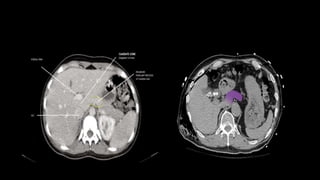

SEGMENTAL ANATOMY OF LIVER

• The French surgeon and anatomist Claude Couinaud divided the liver

into eight functionally independent segments

• allows resection of segments without damaging other segments.

• Each segment has its own vascular inflow, outflow and biliary

drainage.

• In the centre of each segment there is a branch of the portal vein,

hepatic artery and bile duct.

• In the periphery of each segment there is vascular outflow through

the hepatic veins.

• Liver is divided into a functional

left and right liver by a main

scissurae containing the middle

hepatic vein.

• This is known as Cantlie's line.

• Cantlie's line runs from the

middle of the gallbladder fossa

anteriorly to the inferior vena

cava posteriorly.

• Right hepatic vein divides the

right lobe into anterior and

posterior segments.

• Left hepatic vein divides the left

lobe into left medial and left

lateral sections.

• The portal vein divides the liver

horizontally into upper and lower

segments.

• There are eight liver segments.

• Segment IV is divided into segment IVa and IVb according to Bismuth.

• The numbering of the segments is in a clockwise manner.

• Segment I (the caudate lobe) is located posteriorly.

• It is not visible on a frontal view.